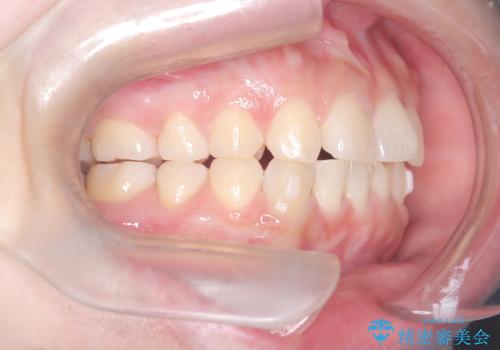

- 「歯の捻じれとがたつき」を主訴に来院された患者様です。

軽度な捻転と叢生だったため、インビザラインのモデレートで治療を行いわずか半年で治療を終える事が出来ました!

目立たないマウスピース矯正【インビザライン】を使用し、

わずか6ヵ月で歯並びがキレイに整いました!

矯正後は、リテーナー(保定装置)を使用し後戻りを防止中です。